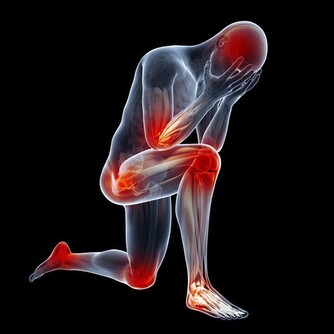

2、多運動

平時多參加一些體育鍛煉,比如太極拳、慢跑、打羽毛球等,都有利提高身體的免疫力,增強血液循環,能起到調節和修復身體的作用,以推遲或延緩大腦和身體的衰老。